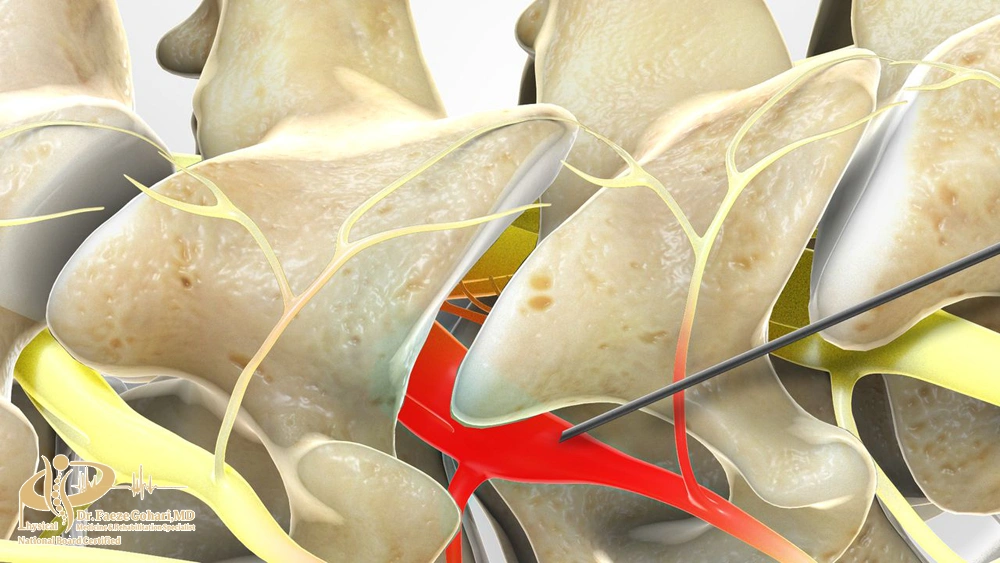

نحوه انجام بلوک عصبی ستونفقرات

بلوک عصبی ستون فقرات به دو روش اصلی انجام میشود: تزریق دارو و رادیوفرکانسی (RF). هر دو روش با هدف مهار انتقال پیامهای درد و کاهش التهاب بهکار میروند، اما در نحوه اجرا و مدت اثر تفاوت دارند. روش تزریقی بیشتر برای تسکین موقت و کمک به تشخیص منبع درد استفاده میشود، در حالی که روش RF معمولاً برای کنترل طولانیمدتتر درد انتخاب میگردد.

در این روش، پزشک با کمک تصویربرداری (فلوروسکوپی) سوزن ظریف را در کنار عصب یا مفصل موردنظر قرار میدهد و داروهایی مانند بیحسی موضعی یا کورتون تزریق میکند. این داروها التهاب را کاهش میدهند و انتقال پیامهای درد را بهطور موقت متوقف میسازند. این روش معمولاً با بیحسی موضعی انجام میشود و بهجز سوزش مختصر یا فشار خفیف هنگام ورود سوزن و تزریق دارو، درد قابل توجهی ندارد. خود تزریق معمولاً ۱۵ تا ۳۰ دقیقه طول میکشد و اثر آن از چند روز تا چند ماه باقی میماند.

- بلوک با دستگاه رادیوفرکانس (RF)

- در این روش، سوزن مخصوص به دستگاه RF متصل شده و در کنار عصب قرار میگیرد. سپس با ارسال امواج رادیوفرکانسی، انتقال سیگنال عصبی مختل میشود. این کار میتواند به دو صورت حرارتی (ایجاد حرارت و قطع طولانیتر پیامهای درد) یا پالسی (کاهش درد بدون آسیب دائمی عصب) انجام شود و اثر آن معمولاً چند ماه تا یک سال باقی میماند. ورود سوزن مشابه روش تزریقی است و بیمار ممکن است در حین فعال شدن امواج حرارتی کمی احساس گرما یا تیرکشیدن در مسیر عصب داشته باشد که قابل تحمل است و گاهی با آرامبخش کنترل میشود. مدت انجام آن حدود ۳۰ تا ۴۵ دقیقه است.